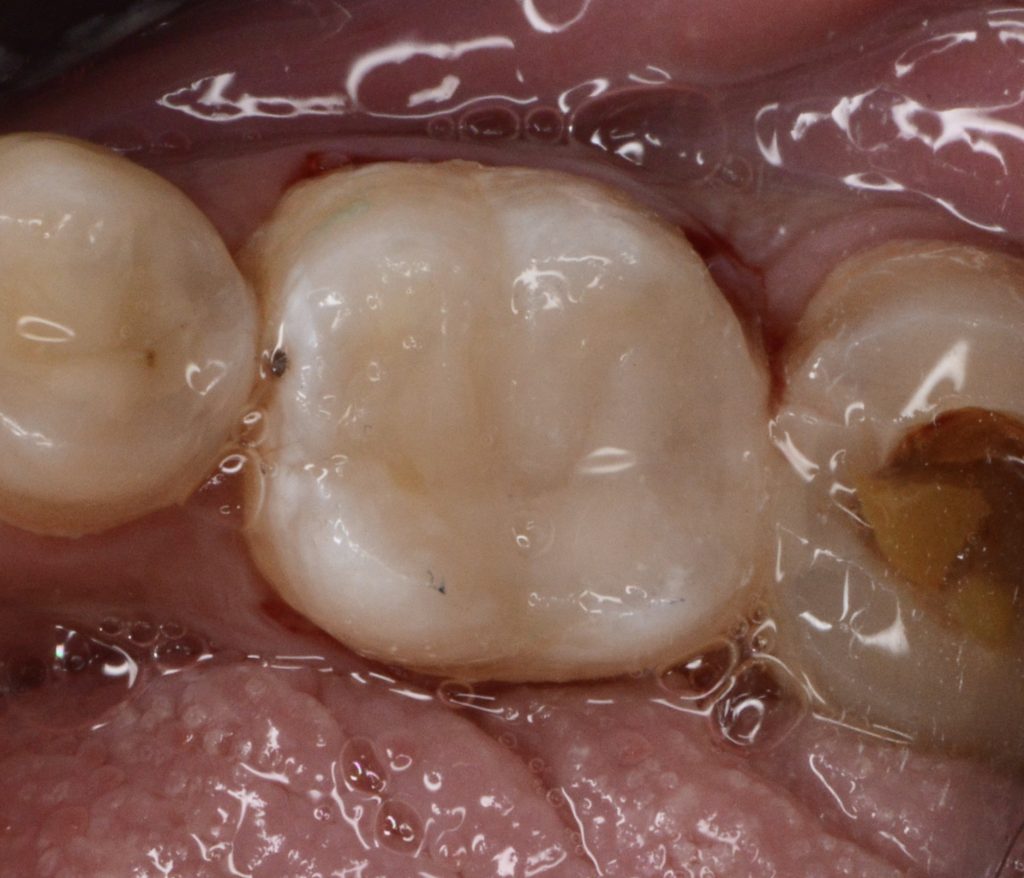

today we’re presenting a direct coronal seal approach using contemporary steps in order to be minimally invasive and keep as much as integral tooth structure as possible, God willing.

(Of course, indirect workflow will help in providing a closer structure to enamel, but the available plan was the direct one in a patient-tailored treatment).